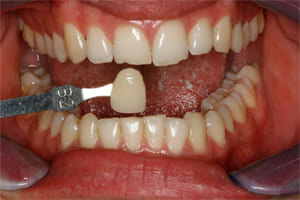

Thank you to our patients that have allowed us to show examples of our work

Have a look at just some of the many patient examples we have captured from BEFORE and AFTER their treatments and cosmetic surgeries.

From Whitening to Veneers, Fillings to Cosmetic Teeth Makeovers, here are some examples of the work that Dr. Dadabhai has provided to his patients to give them a more confident smile and a positive, pain free feeling.

Much of the work we carry out is to relieve pain and of course maintain the health of your teeth and gums, but many of our patients now ask for Cosmetic work to give them a more confident smile.

Cosmetic support has improved hugely over the last few years. Book a Consultation with Dr Dadabhai and he will prescribe a course of treatment to complete your perfect SMILE transformation.